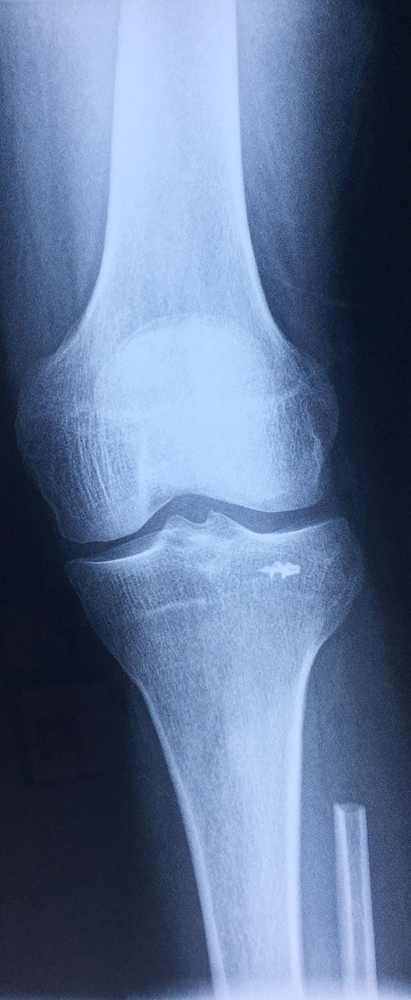

近日,我院关节与骨肿瘤科为一名桡骨远端骨巨细胞瘤Ⅲ级、肿瘤突破间室的男性患者成功实施了肿瘤广泛切除,自体腓骨活骨移植重建桡腕关节术。据悉,对于肢体恶性、侵袭性骨肿瘤,实行广泛外科边界的切除是达到良好的肿瘤学疗效的基础,但这必然会带来肢体结构和功能的更多的丧失。如何既能达到肿瘤的广泛切除,又能最大限度恢复肢体的结构和功能是骨肿瘤外科所追求的目标。肢体结构和功能的生物重建是最接近肢体生理状态的长期有效的重建方式。该方法要求手术者不仅具有精湛的肿瘤外科技术,还要有熟练的显微外科技术,是目前临床上受到普遍推崇的方法。近年来,关节与骨肿瘤科已开展此类手术20多例,取得了良好的效果。